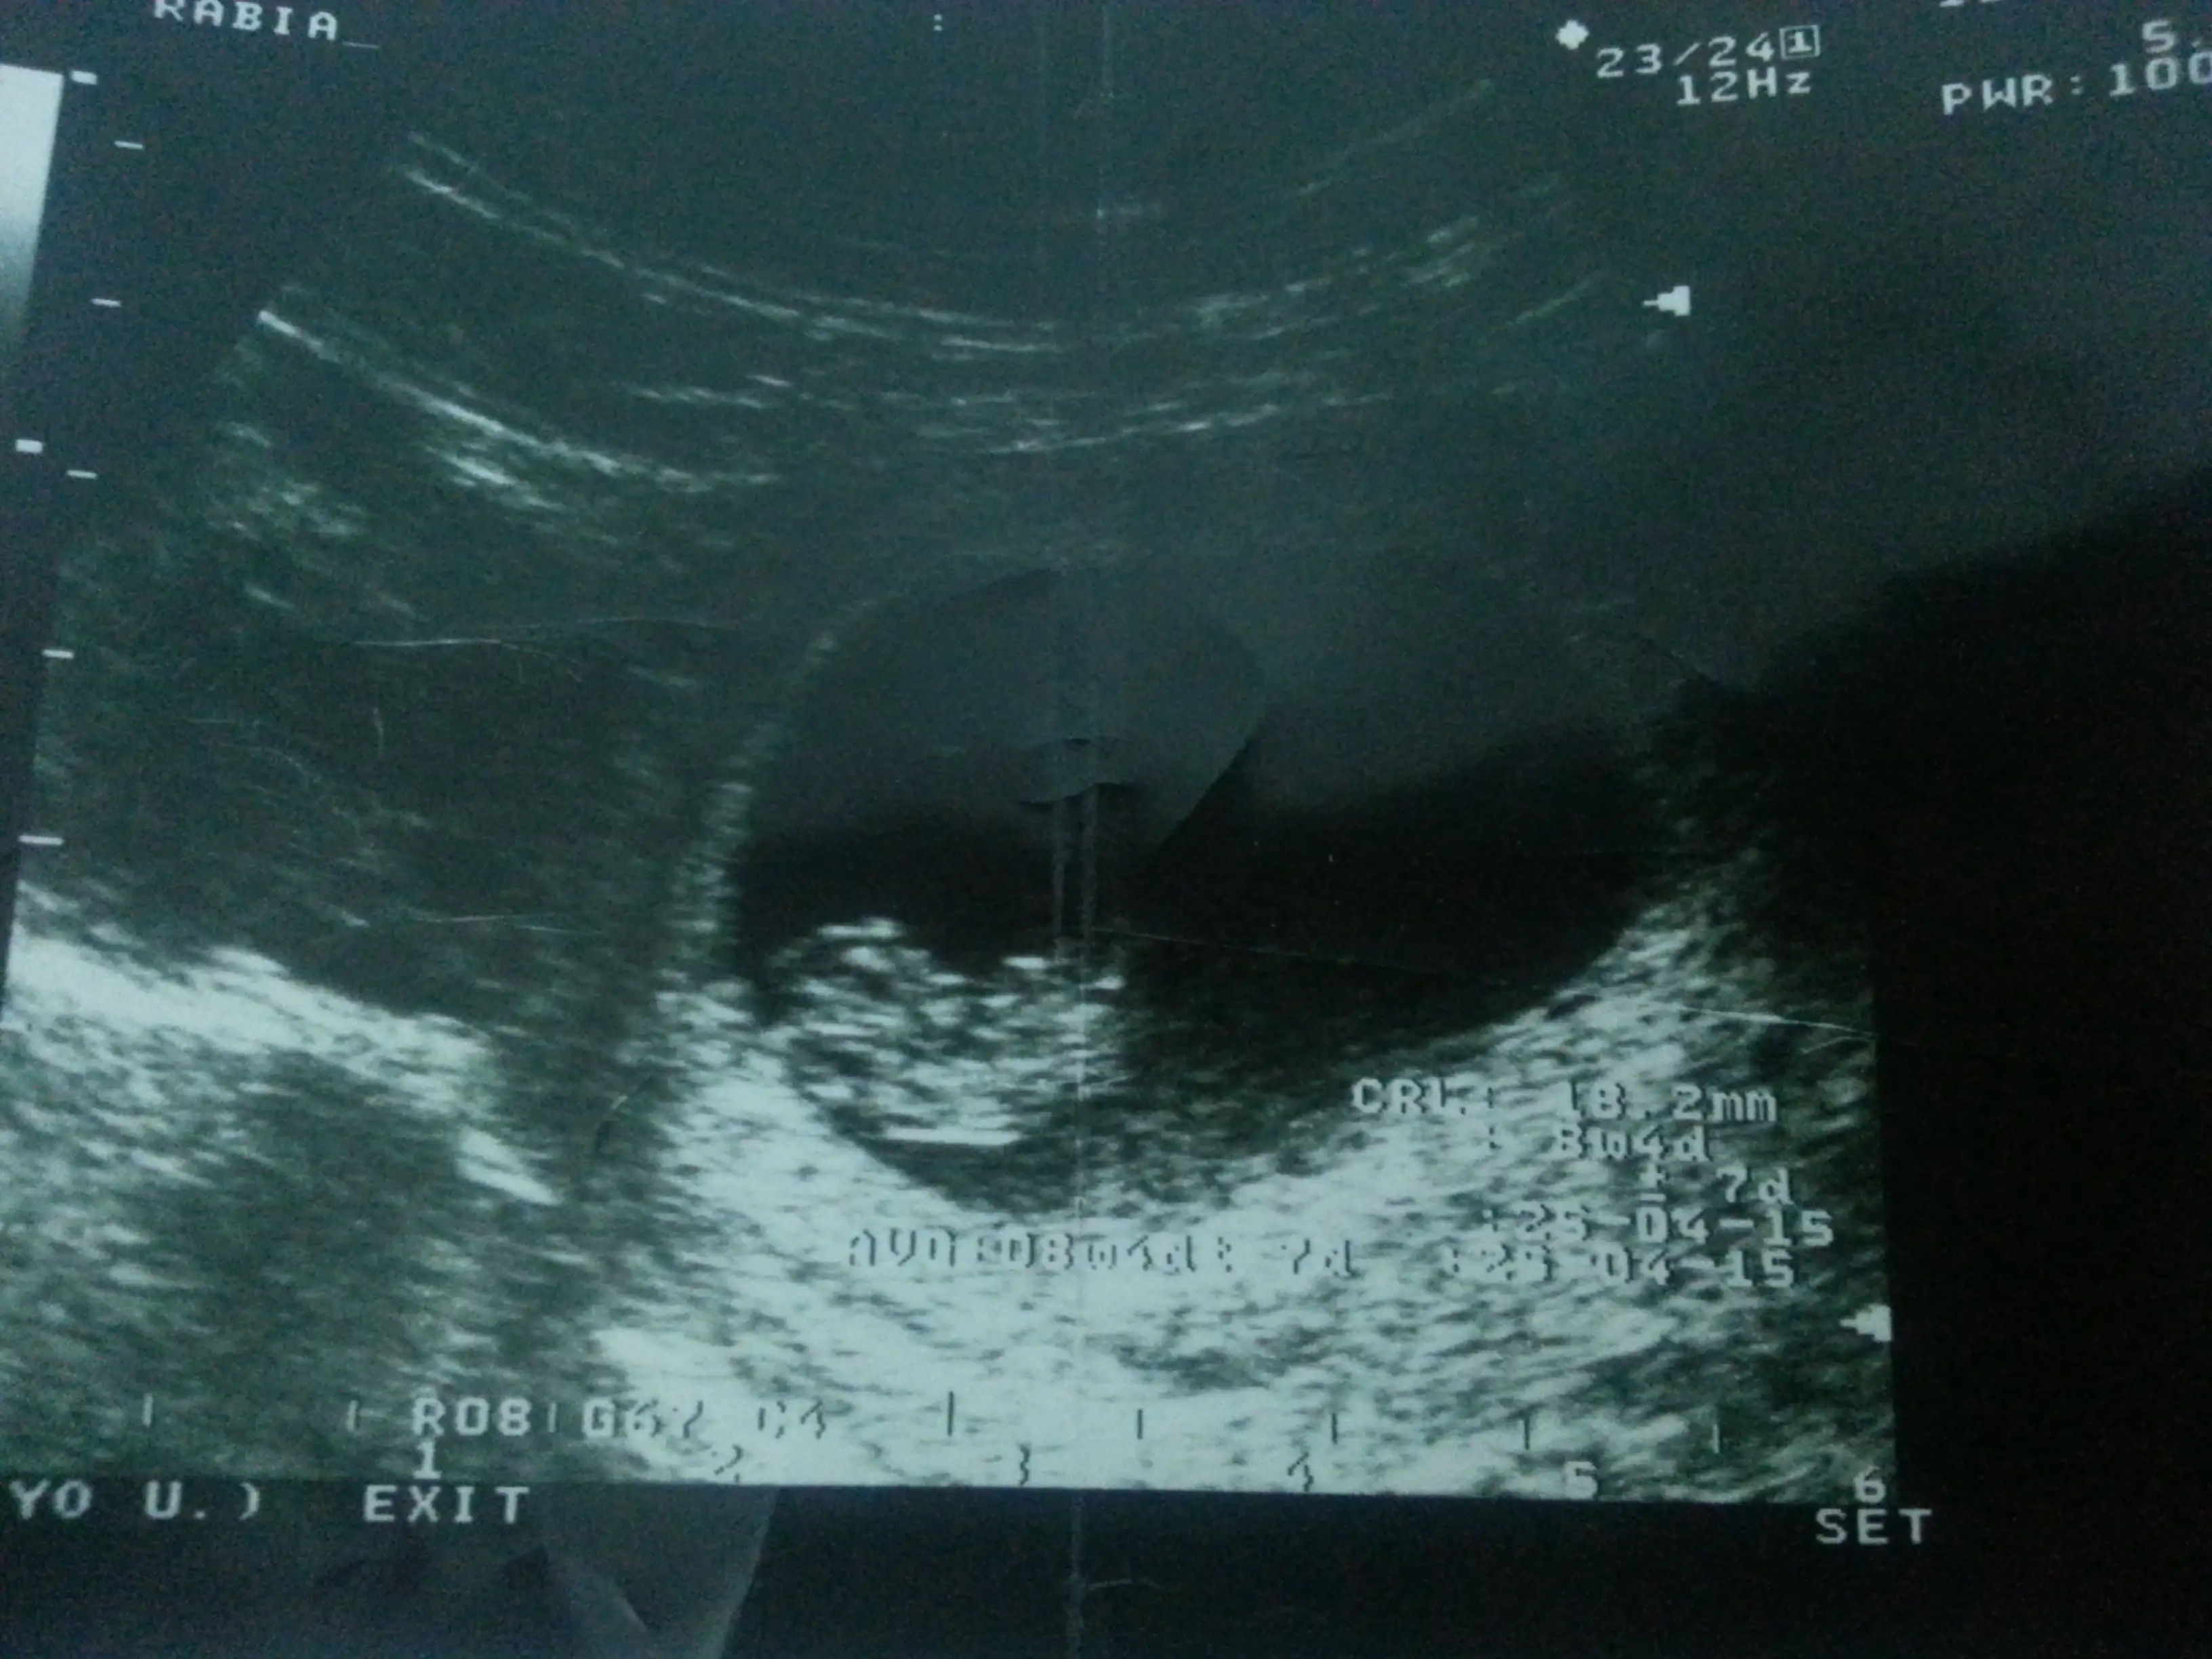

yani o yuvarlak veya oval kese resmin sağında duruyordu demi.birde kesenin içindeki bebeğin yönü var o da mı sağdaydıResme bakınca kesenin sağında yanlışmı bakmışım

pardon yanlış okumuşum.kesenin sağında demişsin zatenyani o yuvarlak veya oval kese resmin sağında duruyordu demi.birde kesenin içindeki bebeğin yönü var o da mı sağdaydı

erkek diyorlar solda olunca ama allah biliyor yinedeBenimki solda 8haftalik ultrason resminde solda gözüküyor gözleri ve minicik ayakları olan bir fasulye ye benziyor sizce cinsiyeti nedir

bizede söyle bakalım öğrenince.teyit edelim.Benimkine bakarmisin bu 8 haftalik ve suan ise 15 haftalik